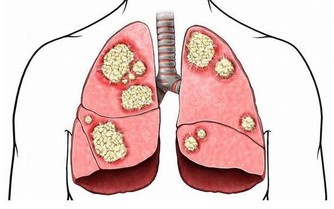

可是,你要當心了,不斷出現腹脹可能是卵巢癌的體徵和症狀之一。

和其他幾乎所有癌症一樣,卵巢癌難以識別,特別是在早期階段。但它終究不是毫無跡象可尋。

而腹脹,就是其中一個警示信號。如果大家了解卵巢癌的各種早期症狀,

比如持續性腹脹,並能儘早把這些症狀與卵巢癌聯繫起來,就會挽救自己或者親朋的生命。